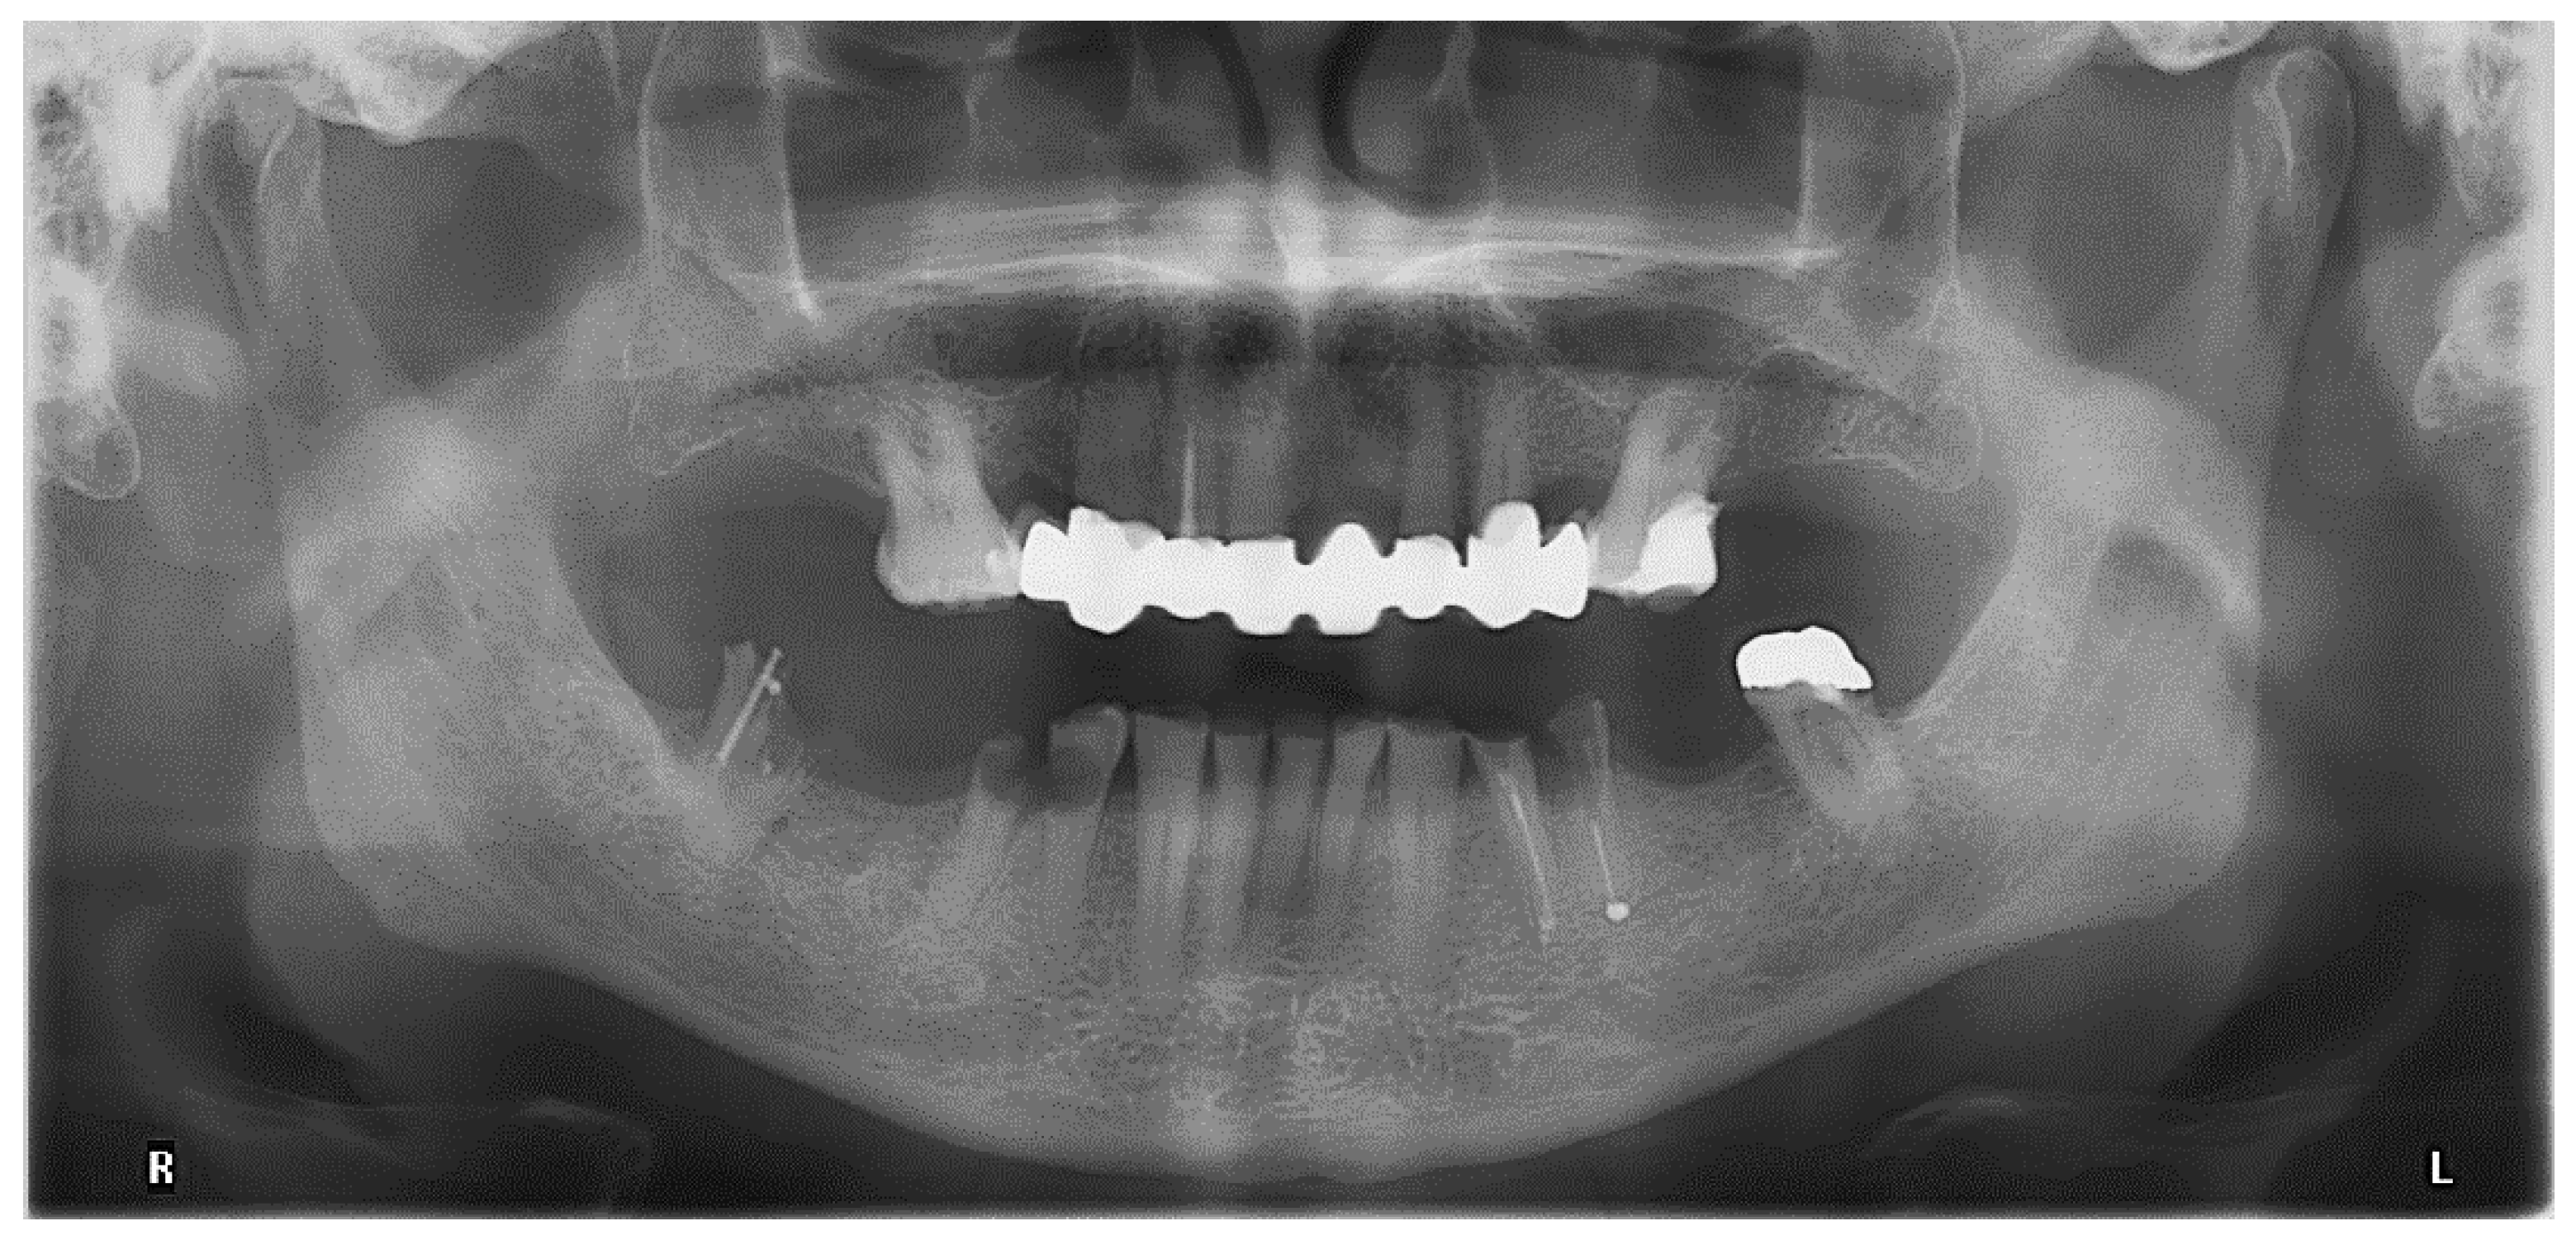

- Locator abutments on both implants, single-crown FDPs on the remaining lower molar teeth, insertion of a tooth-colored and tooth-shaped monolithic RDP fabricated from POM with minimally invasive preparation of the lower anterior teeth (experimental character in long-term endurance).